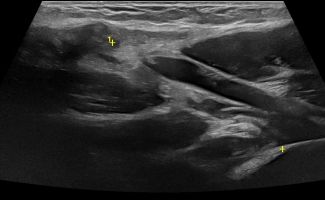

Elbow Ultrasound provides comprehensive imaging of various structures in the region, allowing the identification of pathologic conditions in the joint, bursae, tendons, ligaments, nerves, and soft tissues of the elbow.

- Fluid collection in the elbow joint (i.e. hemarthrosis)

- Fluid collection in the bursa (i.e olecranon bursitis)